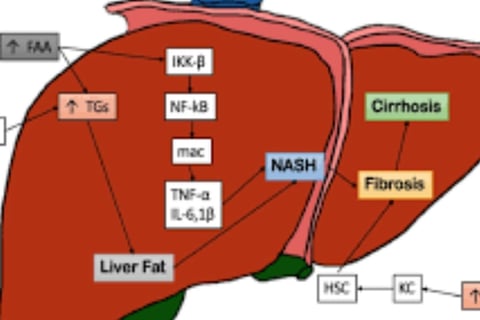

What is the relationship between inflammation and the progression of fatty liver disease?

Inflammation is a key factor in the development of fatty liver disease. Chronic inflammation can damage the liver and worsen the condition.

Fatty Liver: A condition where excess fat accumulates in liver cells, causing inflammation and potential damage.

Non-Alcoholic Fatty Liver Disease (NAFLD): A type of fatty liver not caused by excessive alcohol intake, often linked to obesity and diabetes.